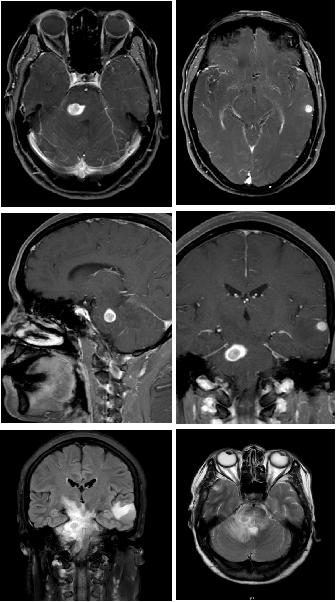

肺癌是严重威胁人民群众生命健康的恶性肿瘤,晚期肺癌患者已错失最佳手术时机,传统的化疗方案对于晚期肺癌患者的总体效果难以满足临床需求[1]。近年来,以PD-1/PD-L1抑制剂为代表的免疫疗法在肺癌治疗中的价值得到积极探索,我国自主研发的PD-1抑制剂替雷利珠单抗在肺癌领域也进行了广泛布局,目前已获批晚期非小细胞肺癌(NSCLC)一线及二/三线治疗适应症,且是唯一实现不可手术局晚及晚期NSCLC医保全程覆盖的PD-1抑制剂。 本期由中山大学孙逸仙纪念医院丁嘉萱医生为大家分享一例替雷利珠单抗用于晚期肺腺癌伴脑转移患者的诊疗过程,并由刘宜敏教授进行点评。该病例中,患者接受替雷利珠单抗治疗已实现超2年持续CR,目前免疫治疗已满两年,遂停止治疗,患者一般情况良好,后续定期影像学随访。 分享专家 丁嘉萱 医生 肿瘤学硕士 中山大学孙逸仙纪念医院放疗科医师 点评专家 刘宜敏 教授 病例详情 基本情况 一般情况:患者女性,53岁。 主诉:因“咳嗽伴气促4月,头痛半月”就诊。 现病史:患者咳嗽伴气促4月,头痛半月,于2020.05我院首诊。 既往史、个人史及家族史:无特殊。 月经婚育史:无特殊。 辅助检查 入院后基线评估: (1)胸部CT示:左肺门区可见一团块状影,大小约42.8mm*30.0mm,边界清,增强扫描呈轻度强化,强化尚均匀,病变包埋左下肺动脉,左肺下叶支气管狭窄,病变下缘可见子灶。纵隔内结构清楚,后纵隔内可见一团块状影,大小约52.8mm*21.0mm,边界清,强化方式与上述病灶相仿,与食管分界不清。双侧肺门淋巴结转移。 入院后胸部CT检查 (2)头颅MRI示:左颞叶、脑干见结节状稍长T1、稍长T2信号影,DWI呈稍高信号,增强后明显强化,周围见片状水肿影,直径分别为8.7mm和11.2mm;左颞叶、脑干异常信号灶,结合病史,考虑转移瘤;全腹MR和全身骨显像无明显异常。 入院后MRI检查 (3)超声支气管镜引导下的经支气管针吸病理活检(EBUS-TBNA):1、左上叶下舌段支气管及左下叶背段支气管,左下叶基底段支气管管腔外压性狭窄;2、隆突增宽;3、纵隔淋巴结转移(第7组,第11L组),EBUS-TBNA细胞病理提示为肺来源腺癌。 于左侧第二隆突探及第11L组淋巴结行EBUS-TBNA (4)免疫组化:TTF-1(+)、NapsinA(+)、CK7(+)、CK5/6部分(+)、Ki67约25%(+),P40(-),PD-L1(22C3)肿瘤细胞约30%(+)、PD-L1(22C3)免疫细胞约20%(+)。 (5)基因检测:RET基因重排。 临床诊断 左肺腺癌伴脑转移(T4N3M1c,IVB期);RET基因重排 诊疗经过 于2020.06.01、2020.06.22、2020.07.13、2020.08.04、2020.08.25、2020.09.15予替雷利珠单抗200mg+培美曲塞800mg+奈达铂110mg治疗6周期;期间于2020.06.04-2020.07.13行WBRT(37.5Gy/15f)+SRS(14Gy),WBRT同期给予替莫唑胺(75mg/m2)。 免疫治疗2周期后复查胸部CT提示:左肺门区肿块较前缩小(21*14mm),后纵隔淋巴结较前缩小(22mm*9mm),左颞叶病灶基本消失、脑干病灶明显缩小(5mm),水肿明显消退。疗效评估为PR。免疫治疗4周期后复查胸部CT,疗效达到CR。 治疗前vs. 免疫治疗2周期后复查胸部CT结果对比 治疗前vs. 免疫治疗2周期后复查胸部CT结果对比 治疗前vs. 免疫治疗4周期后复查胸部CT结果对比 后暂停免疫联合化疗,于2020.09.17-2020.10.30行肺癌累及野放疗(pGTV、pCTV:60Gy/30f)。后于2020.11.12-2022.08.25行替雷利珠单抗200mg+培美曲塞500mg维持治疗23周期。期间定期影像学随访(外院),疗效维持CR。 2021.11.17胸部CT提示:左肺下叶背段及左肺上叶近肺门区团片状密度增高影,其内支气管稍扩张,邻近胸膜可见增厚,同前大致相仿。右肺上叶纵隔旁至近肺门区亦见条片状实变影,部分沿支气管分布,局部支气管稍扩张;右肺中叶内侧段见少许条状影,同前大致相仿。少量心包积液较前稍增多,新见双侧胸腔少量积液。纵隔内见多枚小淋巴结。附见肝右叶后段低密度灶部分向外突出,肝脏余部另见低密度小结节,十二指肠降段见含气囊袋影,同前大致相仿。 2021.12.16头颅MRI(平扫+增强)提示:脑桥右侧区见一小条片异常信号影,T2W1及FLAIR上呈稍高信号,信号较前减低,T1W1上显示欠佳,增强扫描现片未见明确强化,余颅内脑组织形态、信号正常,中线结构居中,脑室系统形态、大小正常,脑池、脑沟及脑裂未见异常,小脑未见异常信号。增强后脑组织强化正常,未见异常信号灶。附见:双侧筛窦及右侧上颌窦黏膜少许增厚。 2022.06.23 PET-CT检查提示:1、左肺癌治疗后,左肺下叶背段及左肺上叶近肺门区斑片状密度增高影伴轻度代谢增高,病灶较前明显吸收,代谢较前减低,考虑放射性肺炎较前吸收、好转,建议追踪复查;2、左侧肺门(10L)及纵隔内(4R、5、7 组)多个小巴结,代谢未见明显增高,结合病史,考虑为淋巴结转移灶治疗后处于明显抑制状态,建议追踪复查;3、脑转移瘤治疗后,颅脑未见明显提示脑转移瘤的高代谢灶,结合病史,考虑脑转移瘤治疗后好转,请结合MRI增强结果。 患者接受免疫治疗满两年(末次治疗时间为2022.08.25),疗效维持CR,与患者充分沟通后,停止免疫维持治疗,定期随访。 2022.11.22头颅MRI(平扫+增强)提示:脑桥右侧区见一小条片异常信号影,T2W1及FLAIR上呈稍高信号,T2W1上显示欠佳,增强扫描未见明确强化,较前大致相仿。双侧顶叶及左基底节区异常信号灶。余颅内脑组织形态、信号正常,中线结构居中。脑室系统形态、大小正常,脑池、脑沟及脑裂未见异常。增强后余脑组织强化正常,未见异常信号灶。附见:双侧筛窦及上颌窦黏膜少许增厚。 2022.12.23胸部CT提示:双肺门区条片状实变影较前缩小、变淡,局部支气管通畅,增强扫描未见明确异常强化灶;右肺中叶内侧段见少许条状影,同前相仿。心包未见积液。纵隔及肺门未见肿大淋巴结;双侧胸腔未见积液。附见肝右叶后段低密度灶部分向外突出,最大横断面约4.4*2.5厘米,增强扫描呈早出晚归强化特点。肝脏余部另见低密度无强化小结节。十二指肠降段见含气囊袋影。 病程回顾 病例点评 该患者在完善相关检查后,最终被确诊为“左肺腺癌伴脑转移、后纵隔与双侧肺门淋巴结转移”。肺癌起病隐匿,约10%-25%的NSCLC患者在确诊时已发生脑转移,约50%的患者在疾病进展中发生脑转移[2]。肺腺癌作为NSCLC的主要病理类型之一,其发病率近年来持续上升[3]。 肺癌脑转移患者的死亡率很高,传统的治疗手段疗效非常有限。数据显示,在未接受治疗的脑转移患者中,中位OS仅为1个月,而接受最佳支持疗法的患者OS约为2个月[2]。近年来,免疫药物及靶向药物的研发问世,大大提高了肺癌脑转移患者的生存率。该患者PD-L1表达阳性,一项汇总分析结果显示[4],对于PD-L1 TPS≥1%的NSCLC脑转移(包括未经治)患者,相比单纯化疗,免疫治疗可改善治疗结局,同时具有更少的不良事件。 有研究表明[5],免疫联合放疗不仅可控制照射区原发肿瘤增殖,同时也能促进肿瘤组织释放抗原形成原位灭活疫苗增加免疫治疗疗效。在一项研究报道中,NSCLC脑转移患者接受免疫联合立体定向放疗安全性良好,不仅降低照射野外复发率,还可提高患者生存期[6]。此外,基因检测提示该患者存在RET基因重排,但我国首个高选择性RET抑制剂获批时间为2021年3月,在该患者2020年6月开始接受治疗时靶向药物暂不可及。 证据显示,免疫联合化疗具有协同增效作用[7],结合该病例具体情况及循证医学证据决定采用免疫联合化疗进行治疗。考虑到该患者为异地就医,为有效管理,提高患者依从性,需选择半衰期长的免疫药物,而我国自主研发的PD-1抑制剂替雷利珠单抗终末半衰期约为26天,达到同类药物最高范围,经MDT讨论予替雷利珠单抗联合化疗,并行WBRT+SRS(WBRT同期给予烷化剂)。近年来,替雷利珠单抗全面布局肺癌领域,积累了丰富的循证医学证据。 RATIONALE 304[8]为一项III期、多中心、随机、开放研究,旨在对比替雷利珠单抗联合化疗和单用化疗一线治疗晚期非鳞状NSCLC的疗效和安全性。在2022 ESMO IO大会上,RATIONALE 304研究公布了最新数据,中位随访16.1个月后,替雷利珠单抗联合化疗组的mPFS进一步延长至9.8个月,显著降低37%的疾病进展风险,ORR达到57.8%,其中CR率提升至4.9%,约为对照组的3倍;mDOR进一步提升至10.6个月,患者获益持久。同时,该研究在此次大会上首次更新了OS数据,联合治疗组的mOS达到21.6个月,HR为0.68,显著降低32%的死亡风险。此外,在RATIONALE 304研究[9]的事后分析中,首次探索了免疫治疗联合化疗的至缓解时间分布,旨在充分了解免疫治疗的反应特征、最大化免疫治疗的临床获益提供了全新思路。结果显示,替雷利珠单抗联合化疗治疗有近50%的应答者在第二次评估后(≥4周期治疗后)出现首次缓解,提示若首次肿瘤评估未达到肿瘤缓解,不必急于停药,继续治疗仍很有可能达到缓解;75%达到CR/PR的患者通过持续治疗,肿瘤会持续退缩,首次缓解到最大肿瘤缓解的中位时间为3.6个月(约5个周期),肿瘤缓解深度更深的应答者,其PFS有延长的趋势,提示已达到CR/PR的患者,持续治疗肿瘤可进一步缩小,实现更长PFS获益。 患者在接受替雷利珠单抗联合治疗2周期后快速达PR,4周期疗效达到CR。6周期后暂停免疫治疗,在针对肺癌累及野放疗后,继续予免疫联合化疗维持治疗23周期,考虑到患者耐受性,在保证疗效的基础上化疗药物(培美曲塞)由标准剂量减量至500mg,以提高生活质量,期间影像学随访疗效维持CR。该患者共接受替雷利珠单抗治疗29周期,截至发稿已实现超2年长生存,充分验证了其在真实世界中用于肺腺癌脑转移患者的有效性和安全性。 根据2020年V1版《NCCN 非小细胞肺癌临床实践指南》,如果患者一线应用免疫疗法,则应接受两年的免疫维持治疗[10],具体临床实践中免疫治疗满2年后继续用药也可持续获益。该病例中,患者自2020年6月开始免疫治疗,至2022年8月已满两年,与患者充分沟通后,停止免疫维持治疗。截至末次随访(2022年12月),患者一般情况良好,未来实现长期生存值得期待。 长期以来,生存期短、预后差的肺癌脑转移患者常被排除在临床试验之外,血脑屏障(BBB)及血液-肿瘤屏障(BTB)等特殊结构也给脑转移相关机制研究造成重重困难[2]。目前,免疫联合放疗还有许多亟待解决的问题,如疗效评价、治疗结合时机、放疗范围及剂量等[5]。期待在未来,该领域能有更深入的研究进展,造福万千肺癌脑转移患者! 参考文献: [1] 王渊, 谭盼, 等. 中国医院用药评价与分析. 2023,23(03). [2] 马力, 朱娅, 等. 中国医药导报. 2023,20(03). [3] 李芳, 韩采利, 等. 肿瘤防治研究. 2023,50(03). [4] Aaron S Mansfield, et al. JTO Clin Res Rep. 2021 Jul 1;2(8):100205. [5] 周冲, 韩亮, 等. 中华转移性肿瘤杂志,2022,05(4):340-343. [6] Kamran A Ahmed, et al. J Neurooncol. 2017 Jun;133(2):331-338. [7] 赵景景, 李玲, 等. 实用癌症杂志. 2022,37(06). [8] Shun Lu, et al. ESMO IO 2022: 138P. [9] Lu S , et al. CSCO 2022. [10] NCCN Guideline NSCLC 2020.V1.